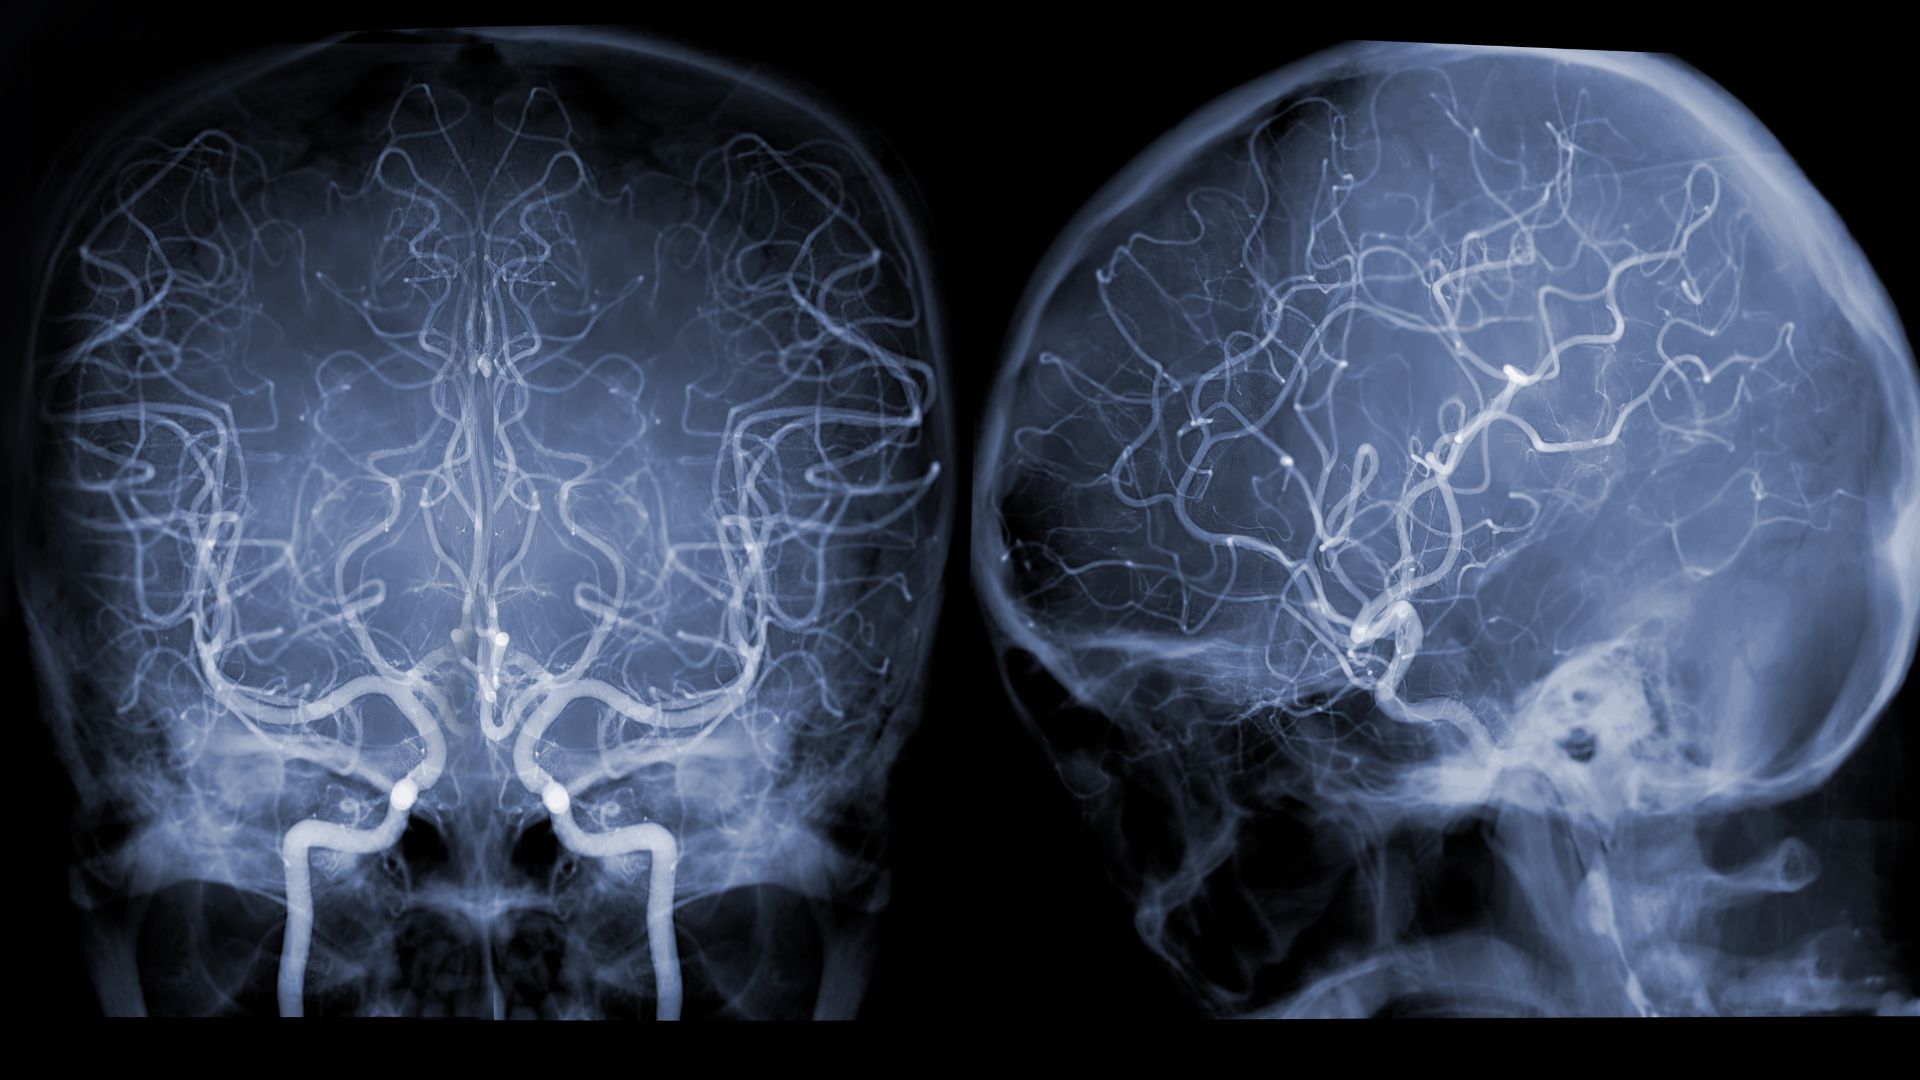

Thiếu máu não là tình trạng giảm lưu lượng máu lên não, làm cho tế bào thần kinh không được cung cấp đủ oxy và dưỡng chất. Điều này gây ra hàng loạt rối loạn về trí nhớ, vận động và tinh thần.

Ngoài ra, một số bệnh lý mạch máu não bẩm sinh như dị dạng mạch máu có thể khiến người trẻ gặp tình trạng thiếu máu não từ sớm mà không biết.

Khám sức khỏe định kỳ là biện pháp không thể bỏ qua. Việc tầm soát huyết áp, tim mạch và mạch máu não giúp phát hiện sớm nguy cơ tiềm ẩn. Người trẻ cần đặc biệt lưu ý nếu có tiền sử gia đình mắc bệnh tim mạch hoặc đột quỵ.